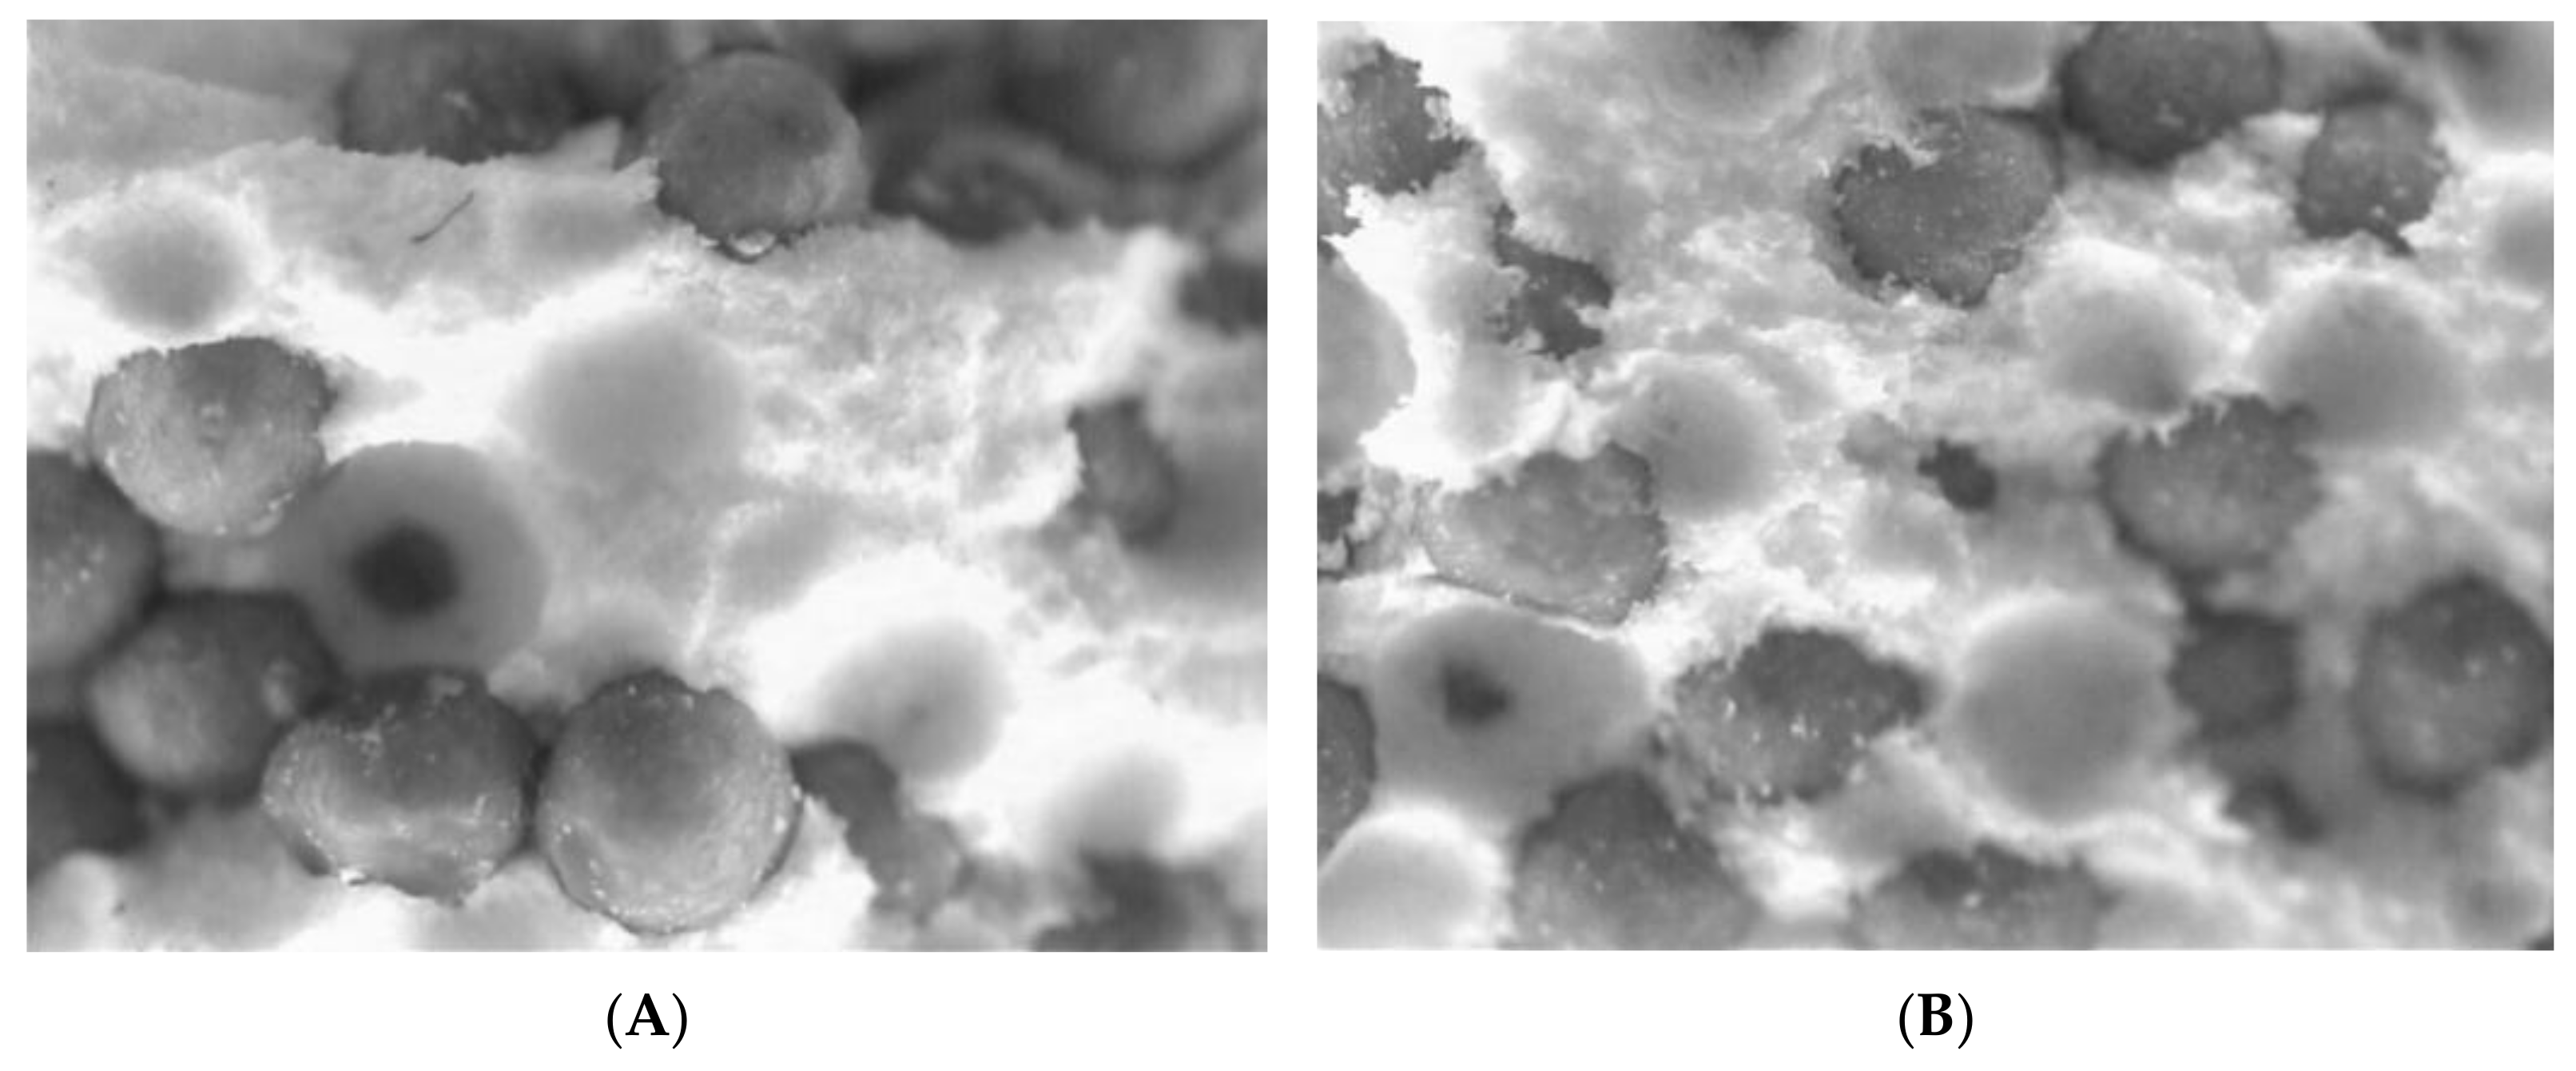

2.2.4. Image Analysis